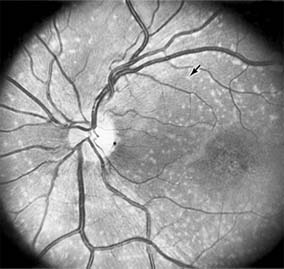

MACULAR EDEMA

Retinal edema involving the macula may be associated with a variety of intraocular inflammatory diseases, retinal vascular diseases, intraocular surgery, inherited or acquired retinal degenerations, medications, macular membranes, or unknown causes. Macular edema may be diffuse, with nonlocalized intraretinal fluid causing thickening of the macula. When edema fluid accumulates in honeycomb-like spaces of the outer plexiform and inner nuclear layers, it is called cystoid macular edema. On fluorescein angiography, fluorescein dye leaks from the perifoveal retinal capillaries and accumulates in a flower-petal pattern about the fovea (Figure 10-4).

Figure 10-4

Figure 10-4: Flower-petal pattern of fluorescein dye in a patient with cystoid macular edema after cataract surgery.

The most widely recognized association with cystoid macular edema is intraocular surgery. Approximately 50% of eyes undergoing uneventful intracapsular cataract extraction and 20% of eyes undergoing extracapsular cataract extraction develop angiographic cystoid macular edema. Clinically significant edema usually occurs within 4-12 weeks postoperatively, but in some instances its onset may be delayed for months or years. Many patients with cystoid macular edema of less than 6 months' duration have self-limited leakage that will resolve without treatment. Topical or local (or both) anti-inflammatory therapy may be of value in restoring visual acuity in some patients with chronic postoperative macular edema. YAG laser vitreolysis (see Chapter 24) and surgical vitrectomy may be of benefit when the macular edema is associated with vitreous tissue incarcerated in the cataract wound or adherent to anterior segment structures. When an intraocular lens implant is the cause of postoperative macular edema due to its design, positioning, or inadequate fixation, removal of the lens implant can be considered.